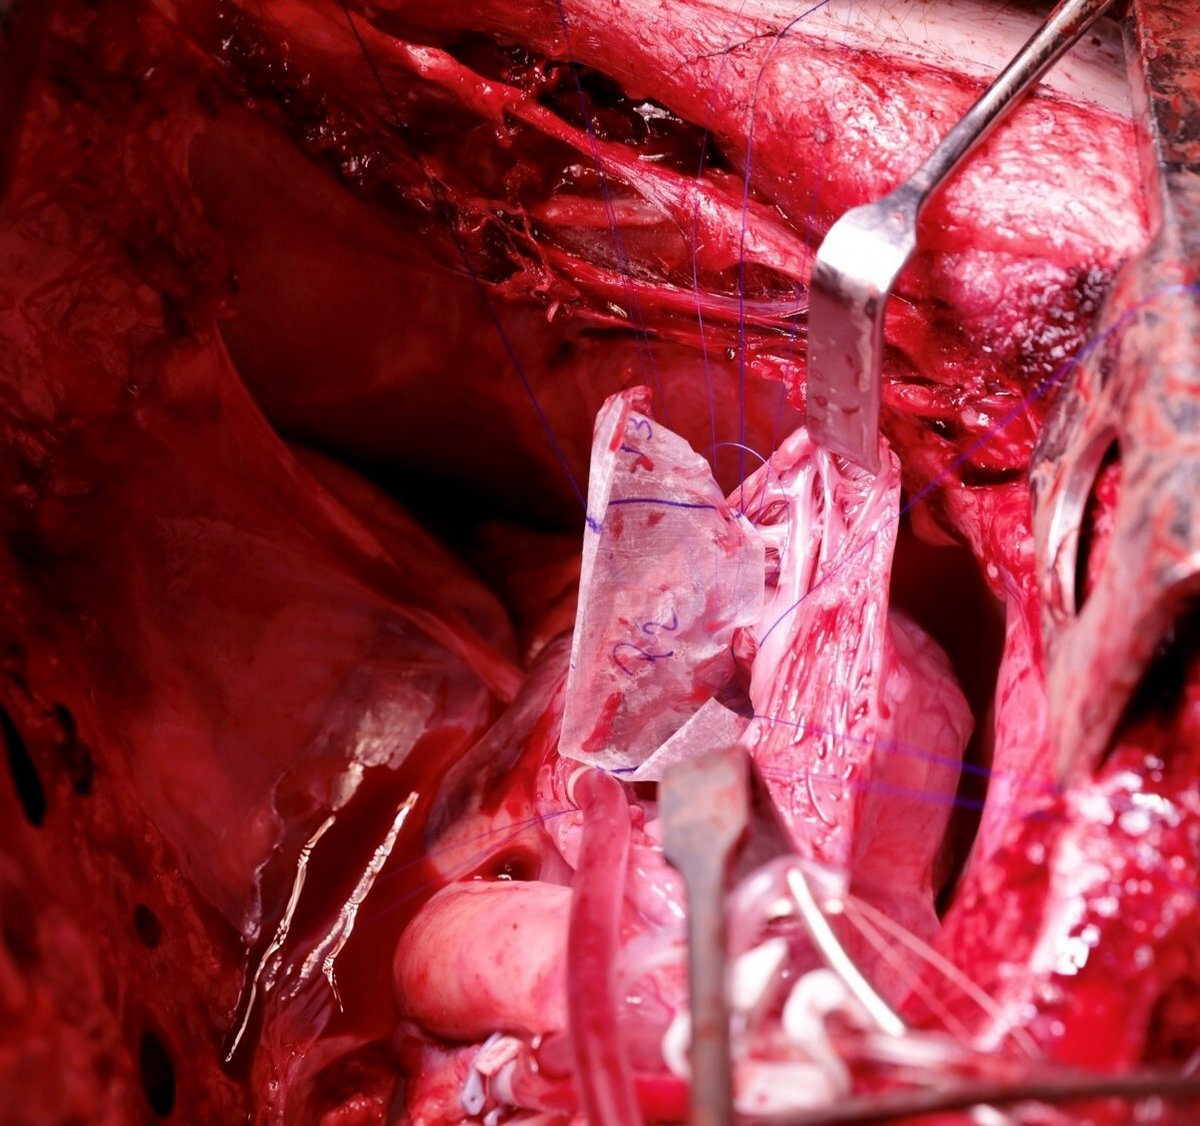

Reconstruction of the Entire Posterior Mitral Valve Leaflet Using Small Intestinal Submucosa Extracellular Matrix

By refining the current surgical treatment options for heart valve disease and developing new ones, we can ultimately provide better, sustained care for patients suffering from heart valve disease. This study in reconstructive mitral valve surgery with bioscaffold materials has the potential and perspective to provide a better and alternative treatment option for many patients - especially patients with severe pathology that would otherwise only be eligible for mitral valve replacement, which has proven subpar compared to mitral valve repair. If our method proves successful, we can offer mitral valve repair for all patients with mitral regurgitation, regardless of pathology. Furthermore, no artificial material will be left in the operated area, which will significantly lower complications associated with heart valve surgery, such as the need for life-long blood-thinner therapy, risk of endocarditis, as well as the potential need for reoperation.

The purpose of this study is to investigate new bioscaffolds for heart valve repair and replacement - both in vitro and in vivo - to validate biomechanical performance and conceive new surgical concepts in mitral valve surgery.